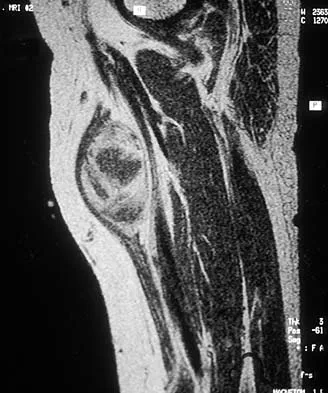

A 17-year-old boy has had a mass in his right thigh for the past 6 months. He denies any history of trauma. Examination reveals that the mass is painless and firm. A radiograph and axial MRI scan are shown in Figures 49a and 49b. What is the most likely diagnosis?